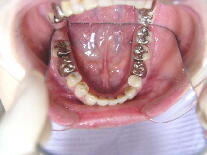

症例1 (10代 女性) 左右上下顎第一小臼歯抜歯例

初診時